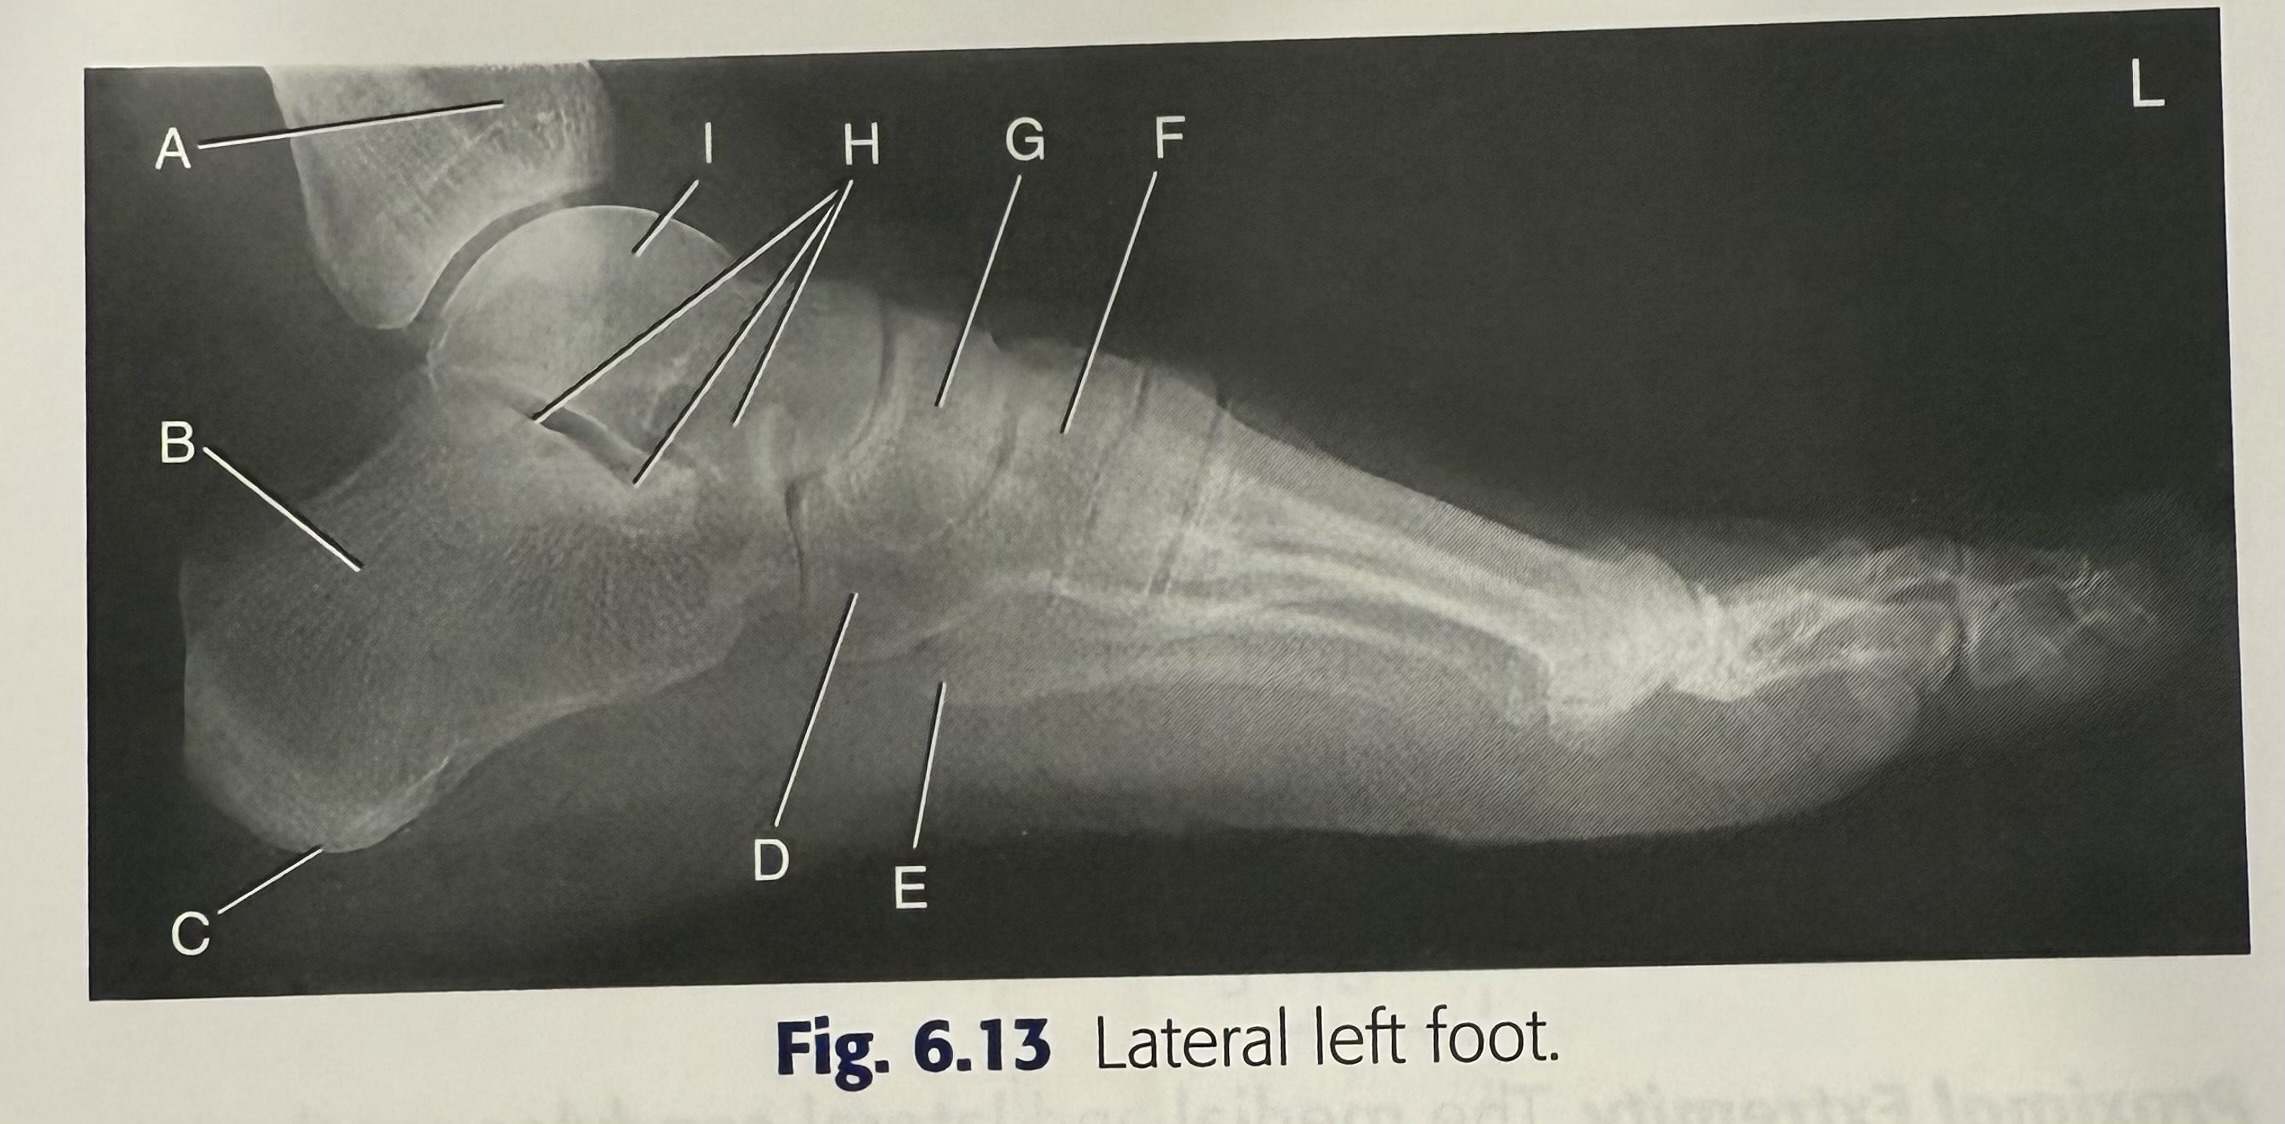

New cards

<p>H</p>

H

talus

14

<p>A</p>

A

cuboid

15